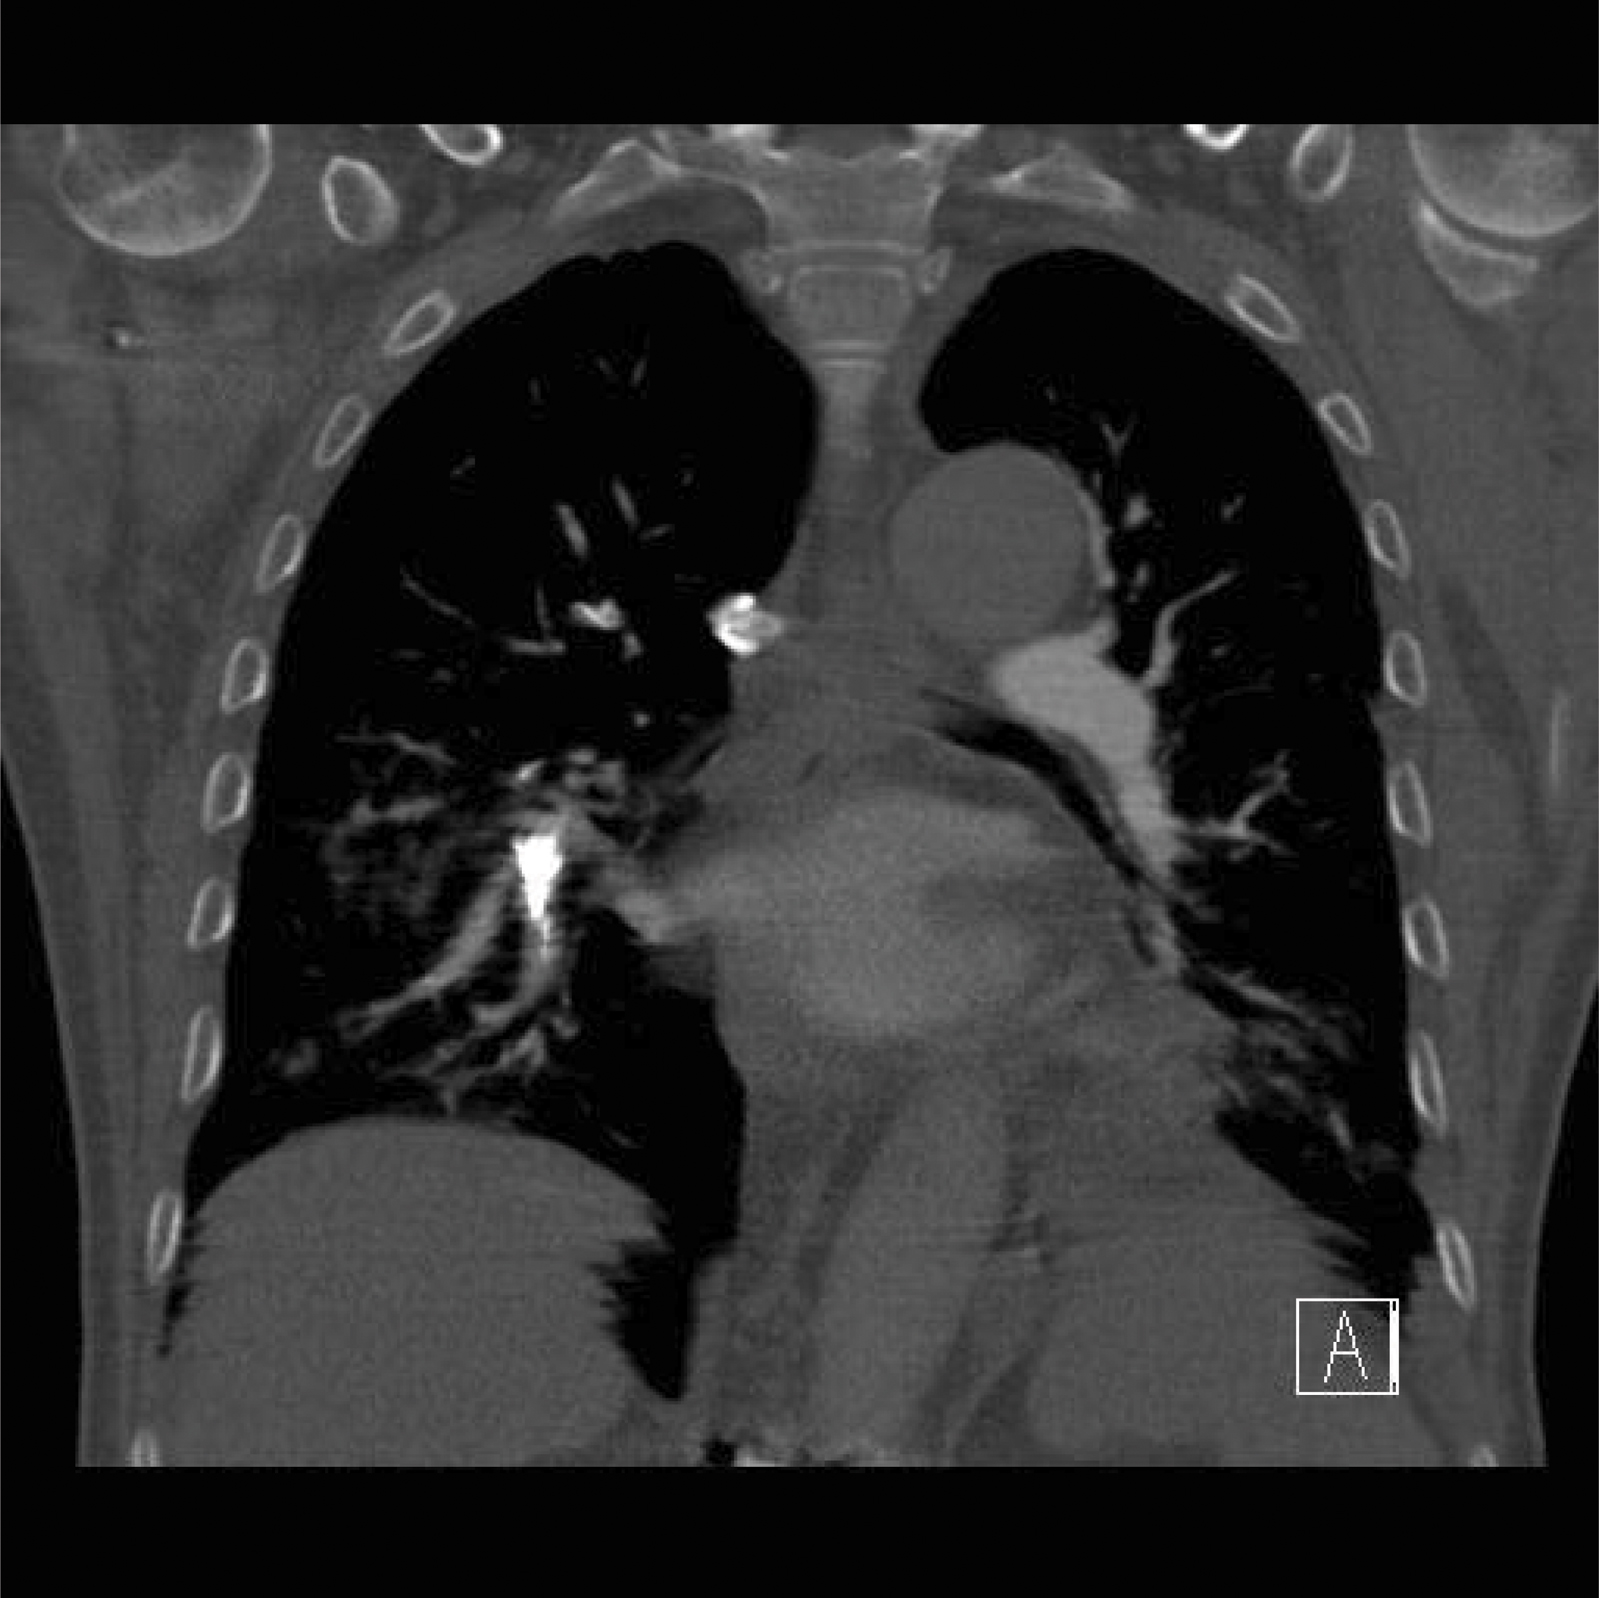

During the six month observation period, no patients died. There were no neurological deficits. On VAS, average pain decreased from 8.5 to 4.1 points postoperativly. The average Cobb angle of 4.1° was improved after surgery. After 6 months, bony consolidation yielded angles of 1 to 4°, average 2.6°. In 42,5% we saw venous extravasation of cement leaking from the augmented vertebrae, even to pulmonary embolism. The emboli were usually asymptomatic.

Only in one case we saw severe reactions.

We report a case where the patient required resuscitation immediately after cement application because of pulmonary emboli. The patient survived because of the immediately-implemented critical care measures.

The risk is little known in the literature, and as yet underestimated despite increasing numbers of augmented fixator operations. Reduction of risk is possible with slower cement injection, smaller cement applicators, and short term positive pressure ventilation with PEEP.

Lung embolism